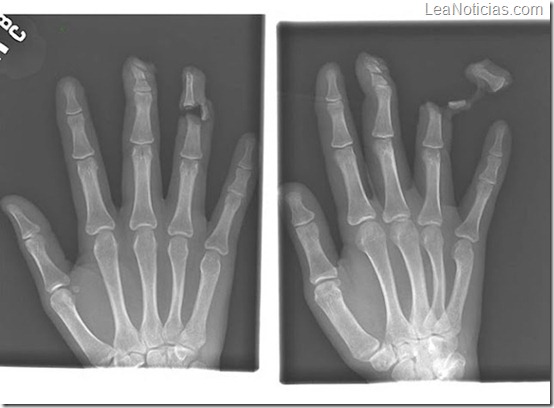

Clavo que atravesó el dedo índice de un adulto por el medio del hueso.

Un paciente con el dedo roto, después de que tuvo una pelea con un hombre armado con un cuchillo.